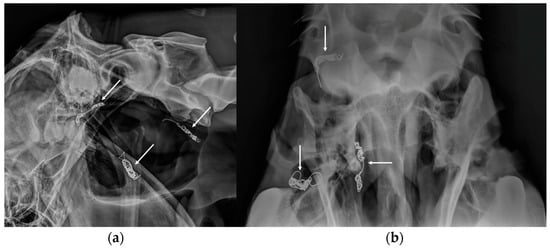

3.4. Temporohyoid Osteoarthropathy